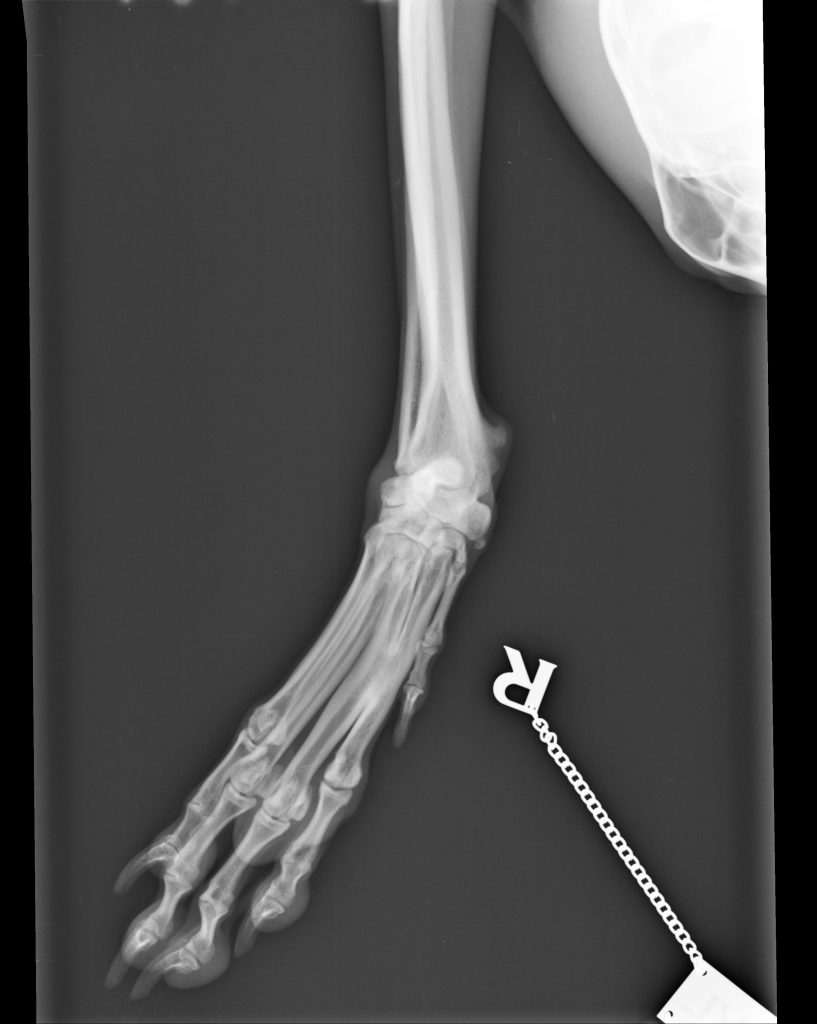

The xrays were shocking, as not only was the wrist fractured ( with the

bones fused) but the leg was also dislocated (90 degrees).

Luckily, this dear brave little hound escaped a front leg amputation, as

the vet was able to open the leg, rotate it, fix the wrist and fit an

external bar to the leg (ex fix).

Luckily, after 3 months, the ex fix was removed with further xrays

showing a secure leg, Mouse made a full recovery.

There was damage to the toes and the other foot but as the damage had

been left untreated for so long and the main damage was fixed,no further

treatment would be necessary, so it meant Mouse could finally have the